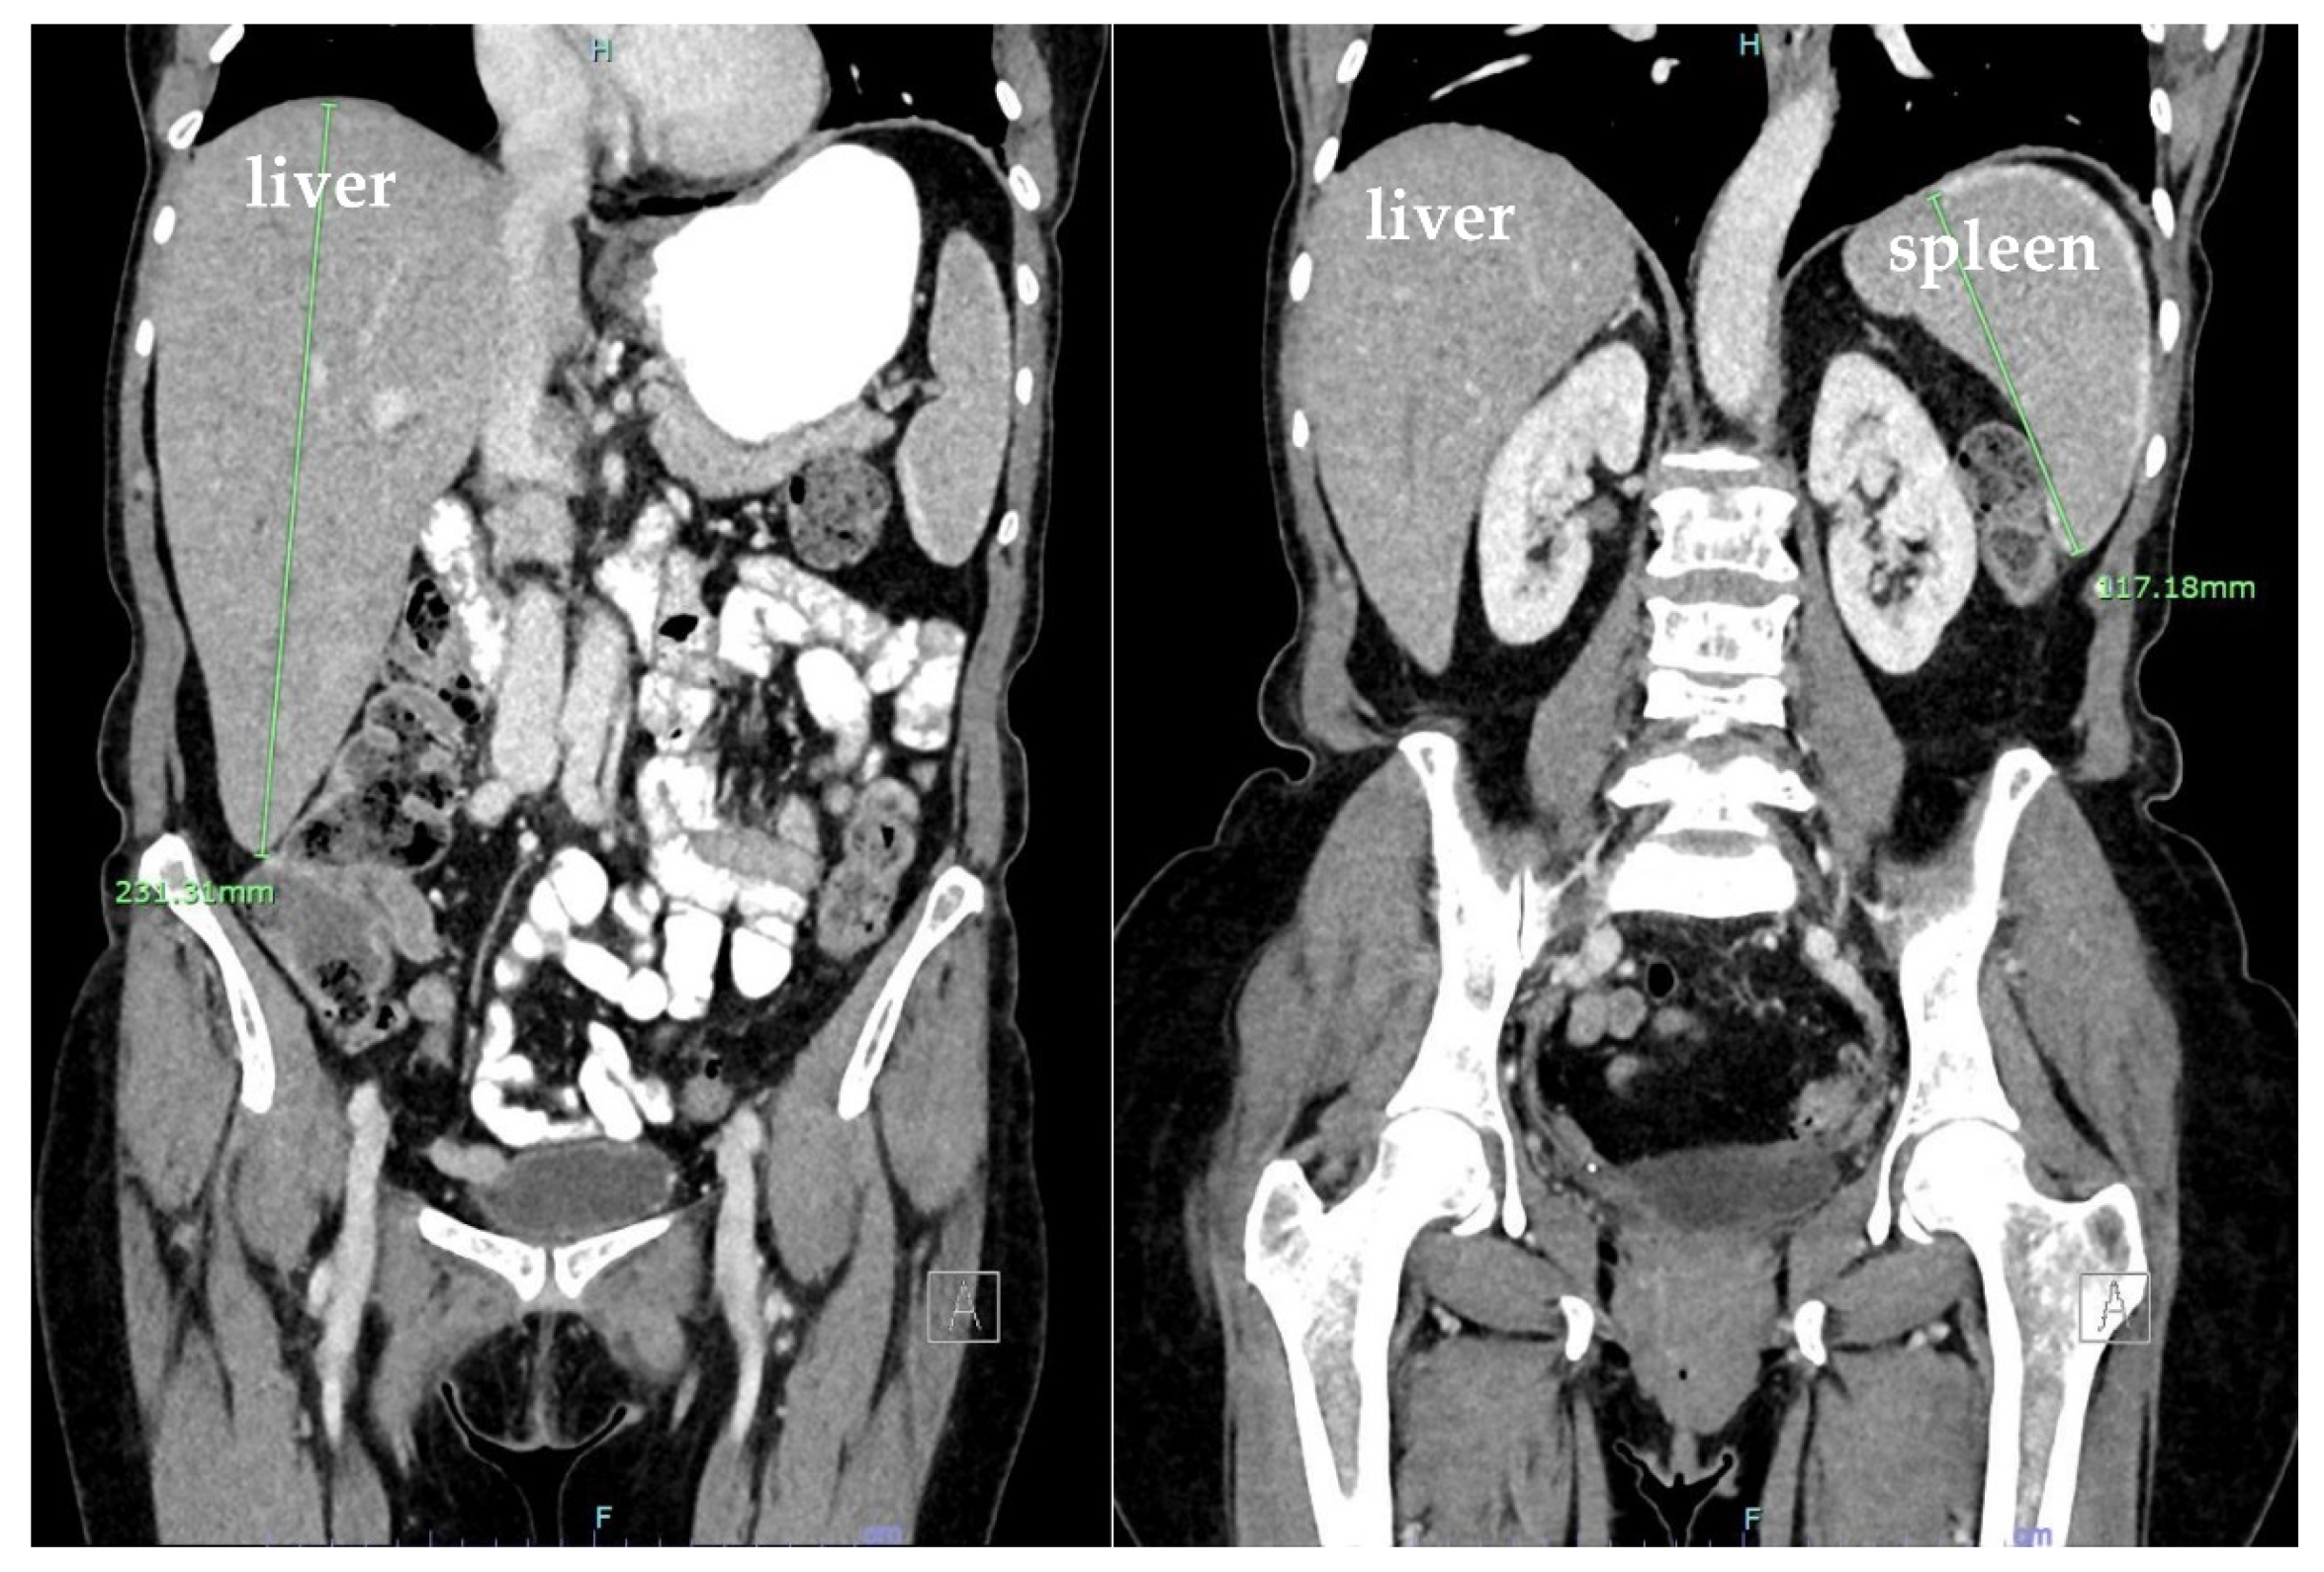

3. Case Presentation

| Buzalewski et al., 2019 [8] | USA | Case report, 68-year-old male | Most common cause of atraumatic splenic rupture is hematologic processes; amyloidosis is rare | Weakness: 1 patient, multiple comorbidities, multiple prior treatments, multiple hematologic diagnoses | CT on admission showed splenomegaly and splenic hematoma, treated with exploratory laparotomy and splenectomy; multiple post op complications; Dx with AL amyloidosis and MM |